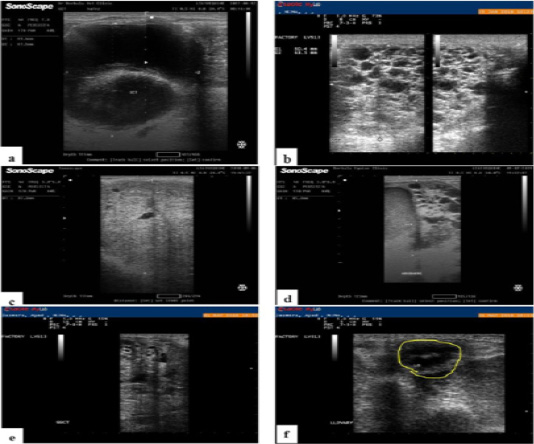

a, Ultrasound image of Arabian mare ovary with granulosa cell tumor showing double large cystic dilatations. b, Ultrasonographic image of Arabian mare ovary with GCT showing multiple cysts with typical honeycomb appearance. c, Ultrasound image of ovary of Arabian mare with granulosa cell tumor. Note the solid mass with few very small cystic cavitations. d, Ultrasound image of Arabian mare ovary with granulosa cell tumor. Note presence of mixed pattern of the tumor. e, ultrasonography showing right ovary with GCT and f, atrophied and non-functioning left ovary of the same case.